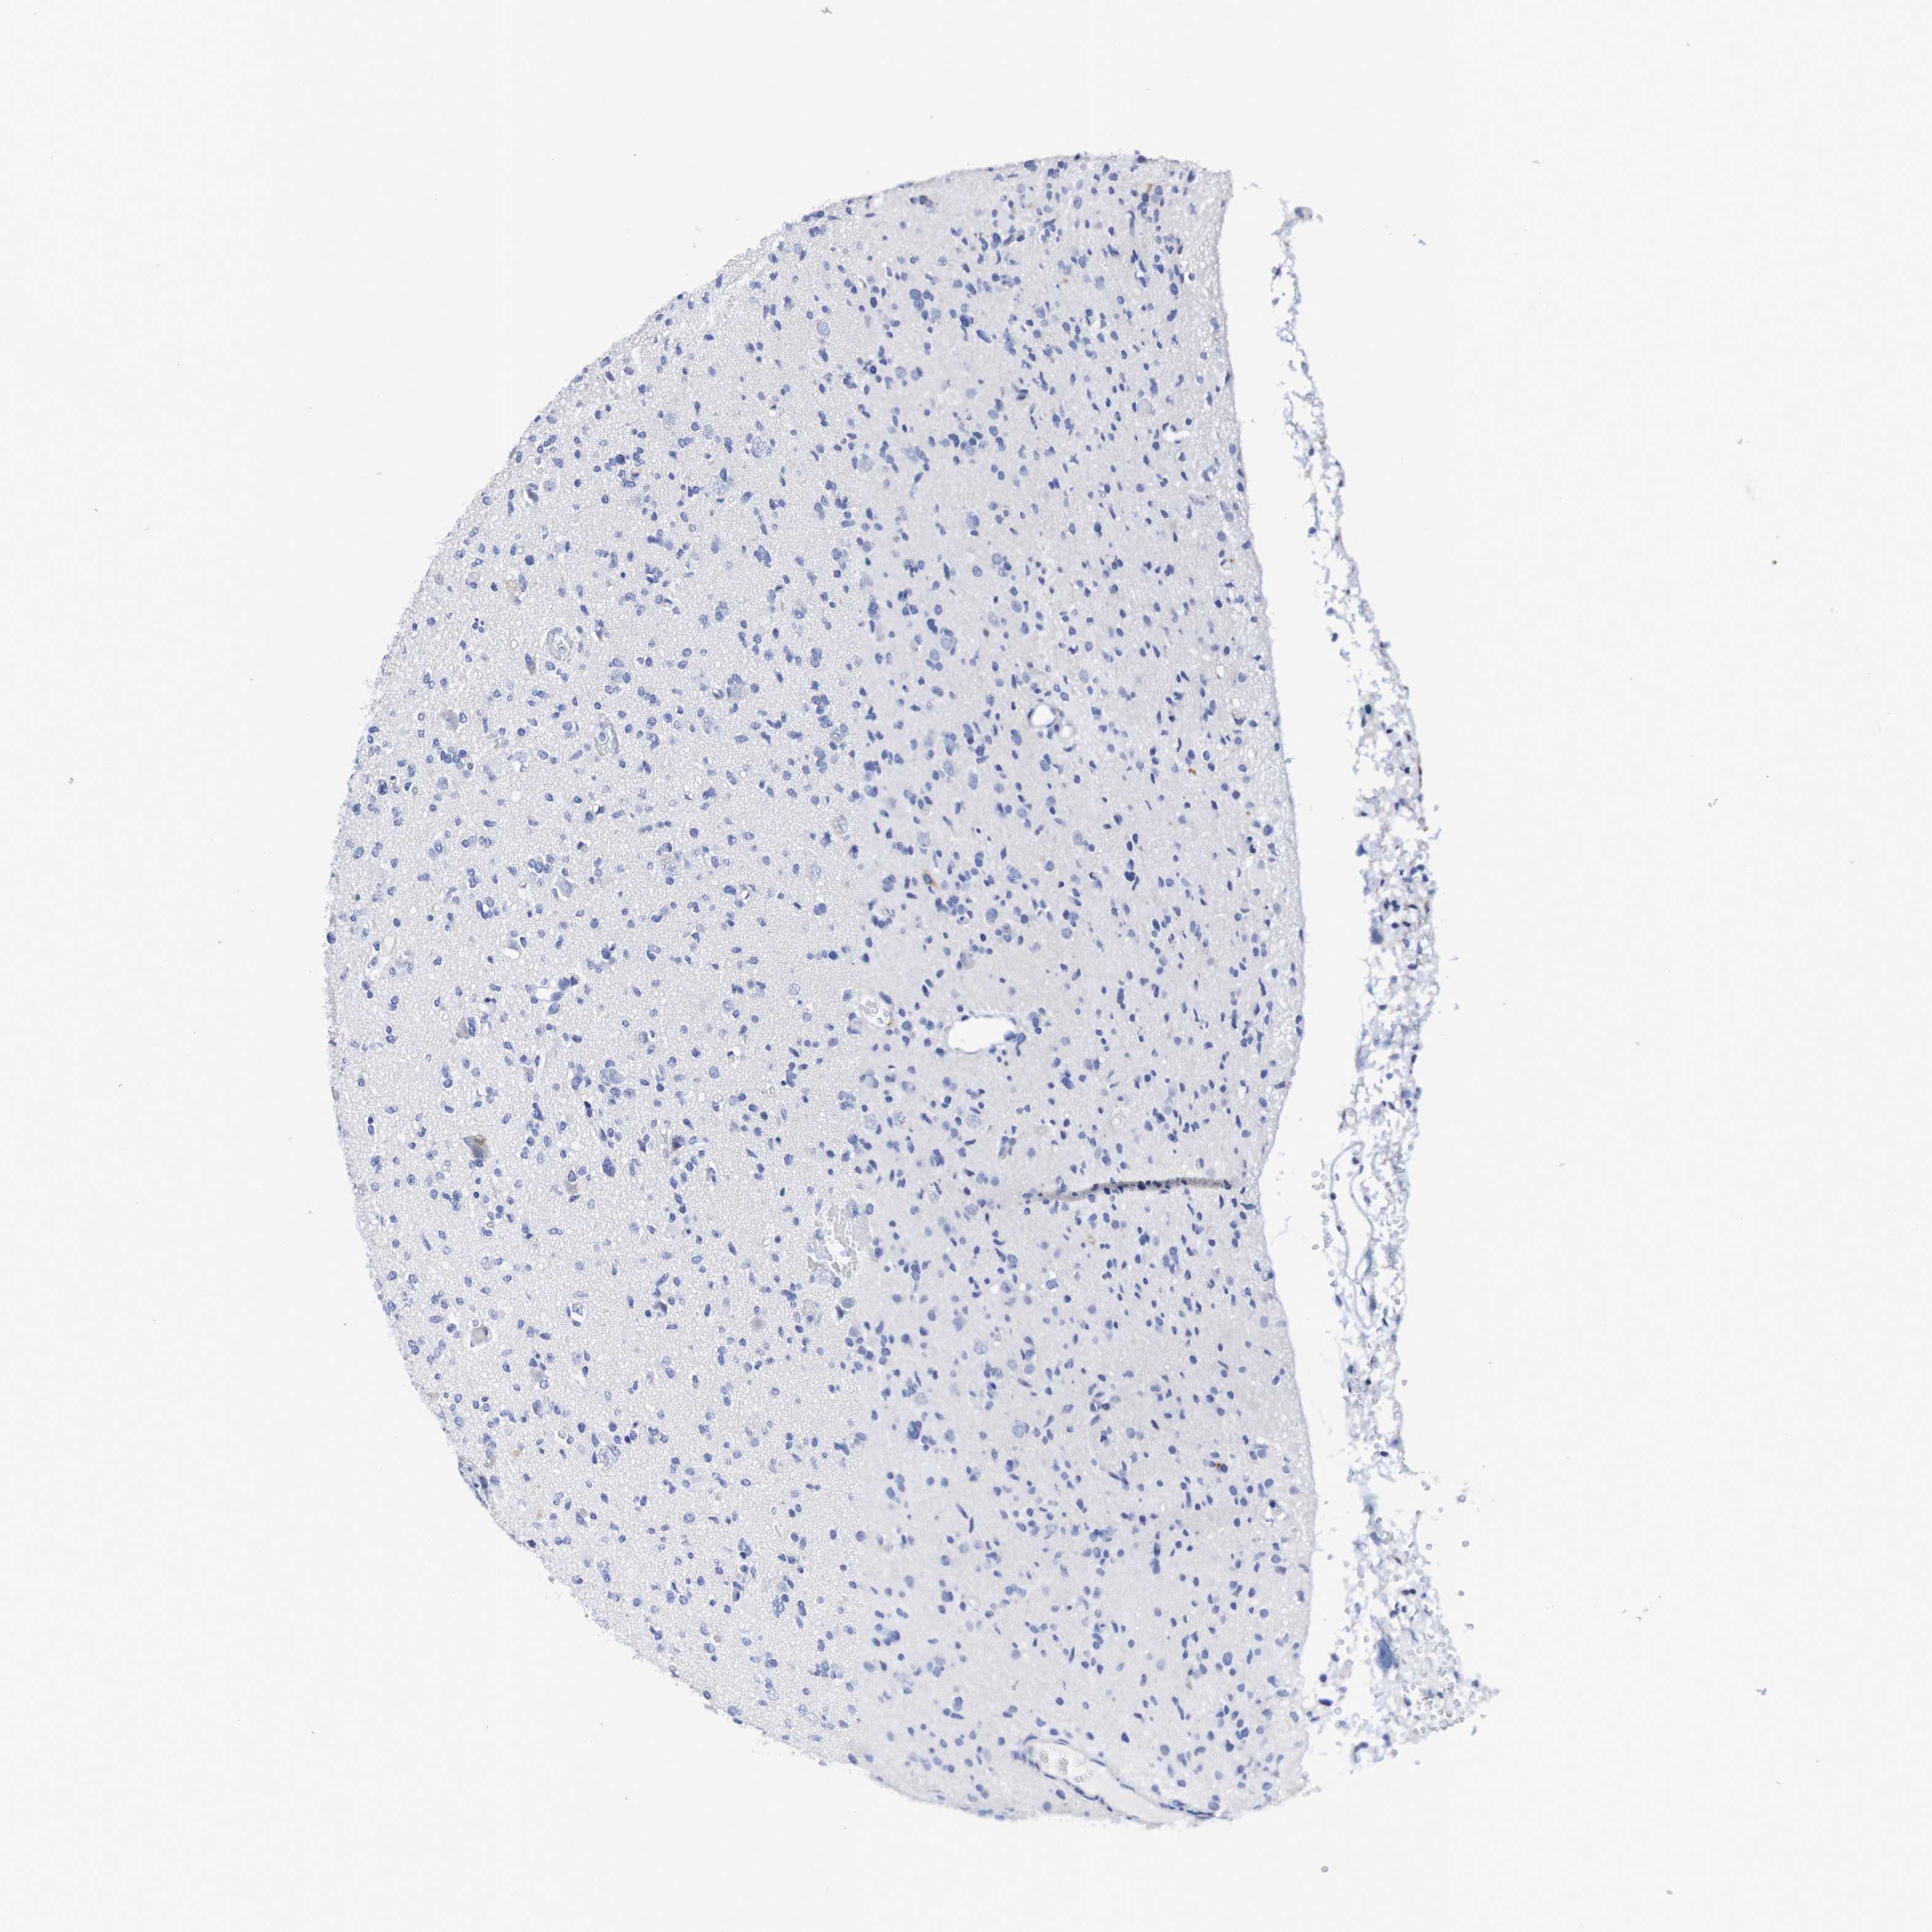

GLIOMA - Protein expressioni

A mouse-over function shows sample information and annotation data. Click on an image to view it in a full screen mode. Samples can be filtered based on level of antibody staining by selecting one or several of the following categories: high, medium, low and not detected. The assay and annotation is described here.

Note that samples used for immunohistochemistry by the Human Protein Atlas do not correspond to samples in the TCGA dataset.

Antibody stainingi

Antibody staining in the annotated cell types in the current human tissue is reported as not detected, low, medium, or high, based on conventional immunohistochemistry profiling in selected tissues. This score is based on the combination of the staining intensity and fraction of stained cells.

Each image is clickable and will lead to virtual microscopy that enables deeper exploration of all samples and also displays staining intensity scores, fraction scores and subcellular localization as well as patient and tissue information for each sample.

Antibody HPA007982

Antibody HPA011933

Glioma, malignant, High grade

Glioma, malignant, Low grade